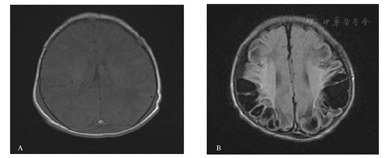

所有入组者住院期间均接受头颅B超或头颅MRI检查。对照组78例患儿中异常8例,异常率为10.26%,窒息组51例,异常27例,异常率为52.94%。轻度窒息患儿头颅影像学检查6例为阳性,重度窒息患儿21例均为阳性。其中:(1)脑组织水肿11例;(2)基底节-丘脑损伤(轻、中、重度)3例;(3)白质损伤(局灶型、广泛型、弥漫型)16例;(4)颅内出血(脑室管区-脑室内出血、脑实质出血、蛛网膜下腔出血)13例。1例重度缺血缺氧脑病患儿的头颅MRI检查结果见图2。

A.出生后5 d脑水肿;B.出生后20 d脑软化。